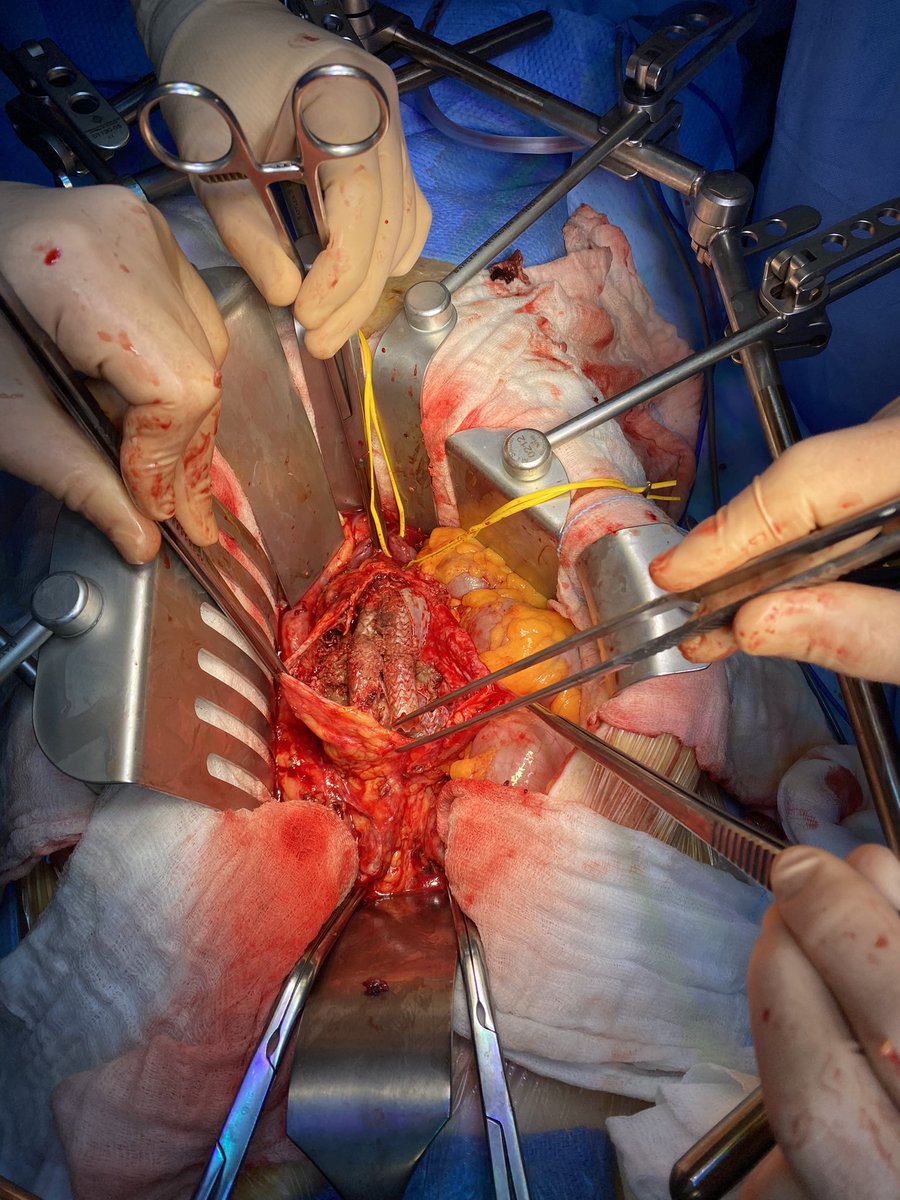

Type II endoleak with progressive sac enlargement. The first #inthebucket of 2024! 🗑️ #veterosurgery

“Get together”…sometimes “Open Repair” need to be done after/with EVAR. Surgical option. Type I refractory endoleak. FEVAR not possible due to tortuosity, calcification and diameter of the external iliac.#vascularsurgery #hospitaldasclinicasribeiraopreto #aorta #aneurysm #usp

Type IA 120x130mm symptomatic. #veterosurgery #inthebucket